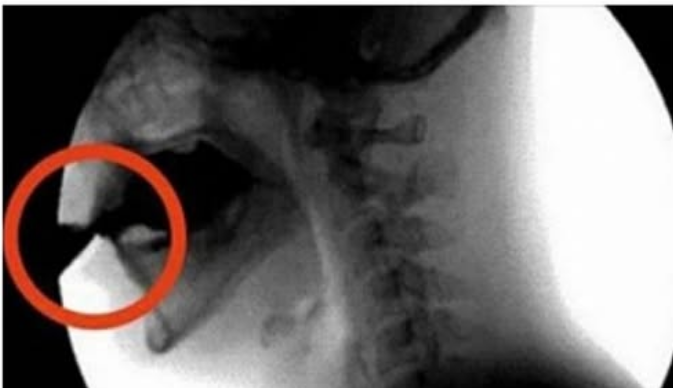

Tijelo ima ograničen broj esencijalnih hranjivih tvari, posebno kalcija, koji je ključan za zdravlje crijevne stijenke. Nakon sat vremena: Dehidracija tijela je očita. Kofein je sposoban pokazati svoja diuretička svojstva, što uzrokuje povećanje volumena mokrenja. Ishod? Tijelo izbacuje ne samo višak tekućine, već i potrebne minerale poput kalcija, magnezija i cinka. Ovi minerali važni su u brojnim procesima, uključujući zdravlje kostiju i pravilno funkcioniranje mišića i srca.